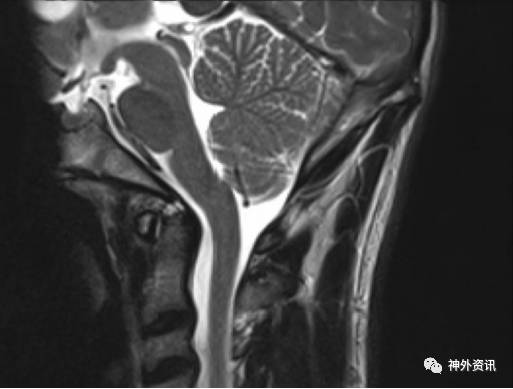

作者回顾性分析50例诊断为Chiari I型畸形的小儿患者,年龄2-21岁,平均9.3岁。在MRI矢状位和冠状位上测量和比较小脑扁桃体下疝情况(图1、2、3、4)。

图3. MRI矢状位成像,枕骨大孔小脑扁桃体下疝6毫米。

50例患儿中,48例在MRI冠状位发现小脑扁桃体不对称,左侧扁桃体下疝最大值为20.9毫米,右侧扁桃体下疝最大值为17.4毫米。MRI矢状位上,小脑扁桃体下疝范围从5-27.4毫米不等。5例(10%)患儿在MRI冠状位发现双侧小脑扁桃体下疝至枕骨大孔下长度小于3毫米,19例(38%)在冠状位上一侧小脑扁桃体下疝小于3毫米。但在MRI矢状位上扁桃体下移都超过3毫米,而每例患儿在MRI正中矢状位上的小脑扁桃体下疝均大于3毫米。作者依据测量的结果认为,Chiari I型畸形常常是不对称的小脑扁桃体下疝。如果仅在MRI正中矢状位上测量,小脑扁桃体下疝可能会造成误诊。因此,不应采用单一的MRI矢状位成像诊断Chiari I型畸形小脑扁桃体下疝的程度。